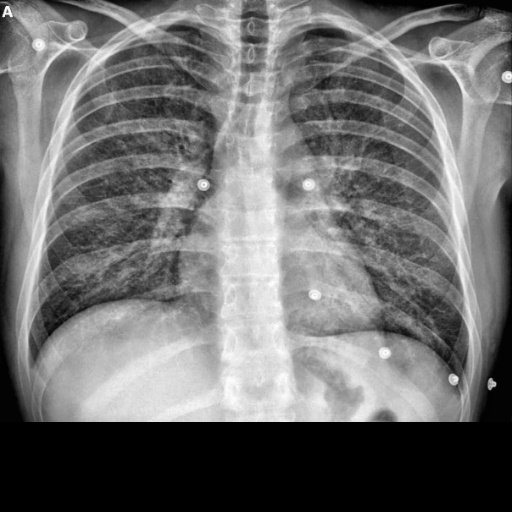

where is the pixel’s new gray level value, the values and are the pixels with the lowest and highest values low in the neighborhood and corresponds to the cumulative distribution function [38]. In Fig. 2 we present an example with the original and preprocessed image.

(A) | (B) |

---|---|

![]() |